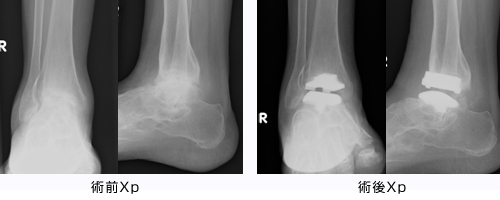

.jpg)

- 関節リウマチに伴う足関節変形に対して、人工足関節置換術(Total Ankle Arthroplasty, TAA)を施行。→ 疼痛なくなり、スムーズに歩行可能となった。